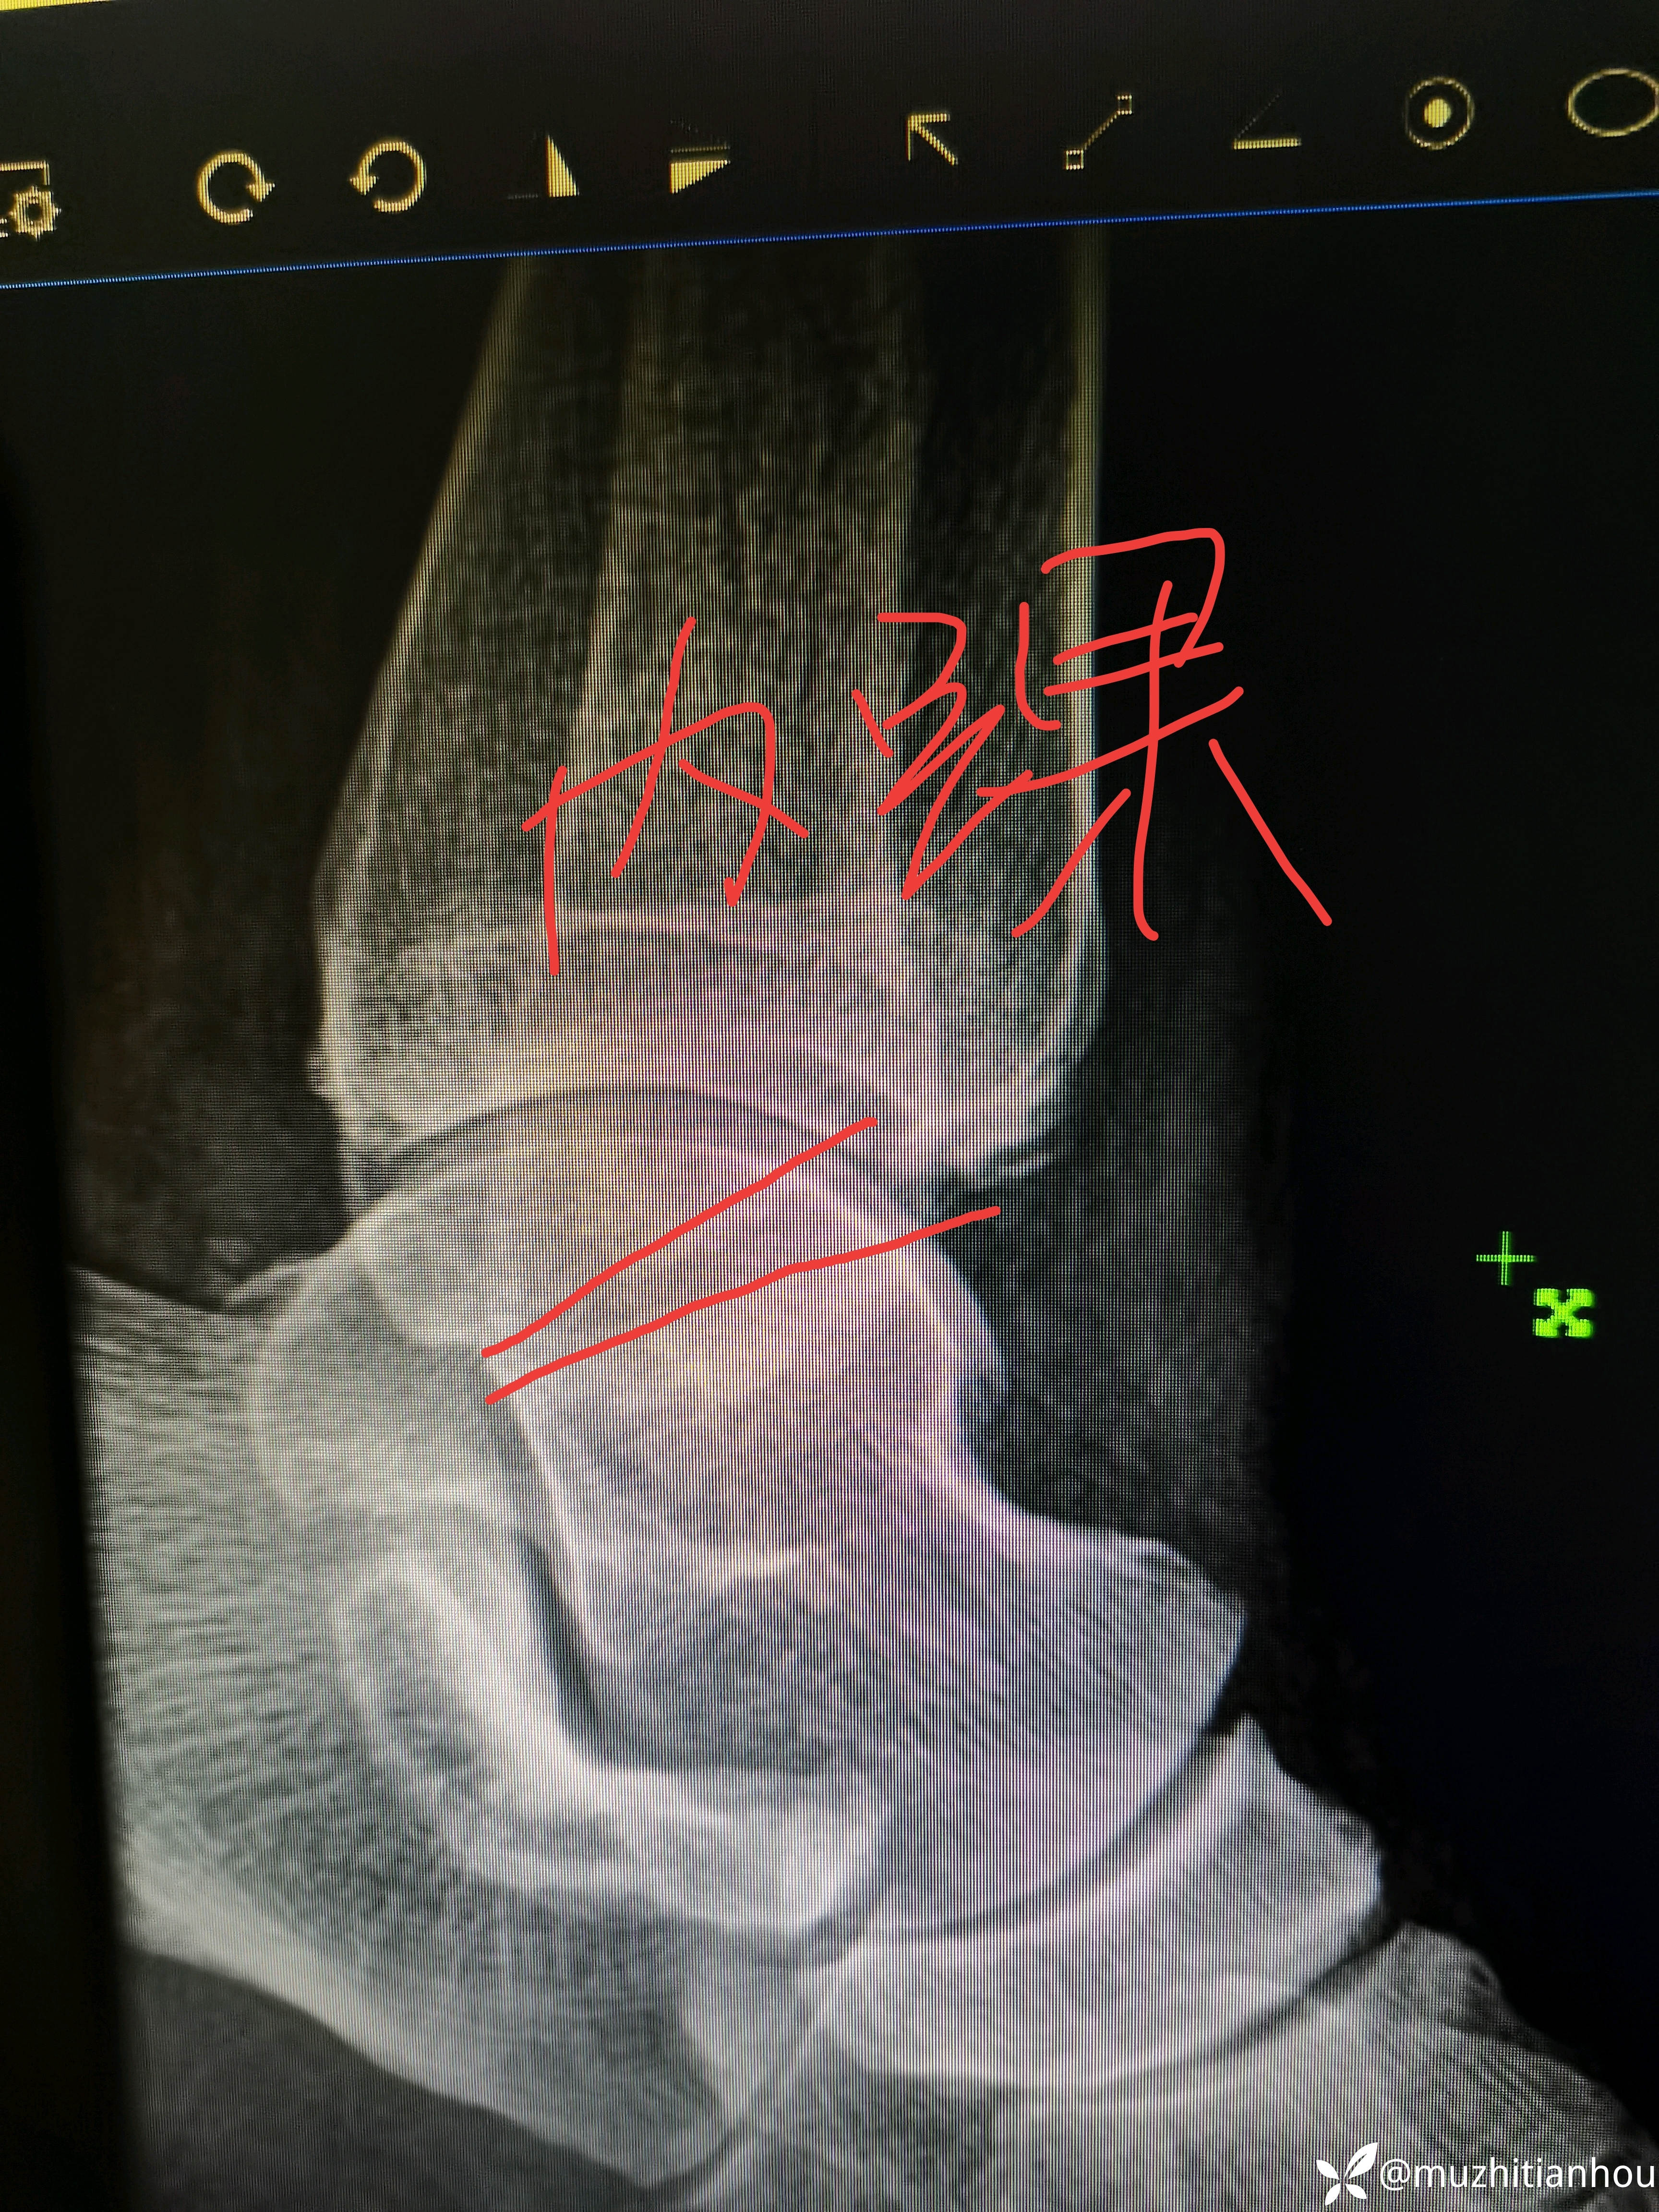

看着腓骨长度没问题,旋转没问题,踝穴也可以,这个岁数是不是可以保守的?

侧位没经验的大夫会不会看内踝呢?有什么端倪吗?门诊碰到这样的患者问你能不能保守治疗,你会怎么处理?

返回头来再看会不会有收获呢?